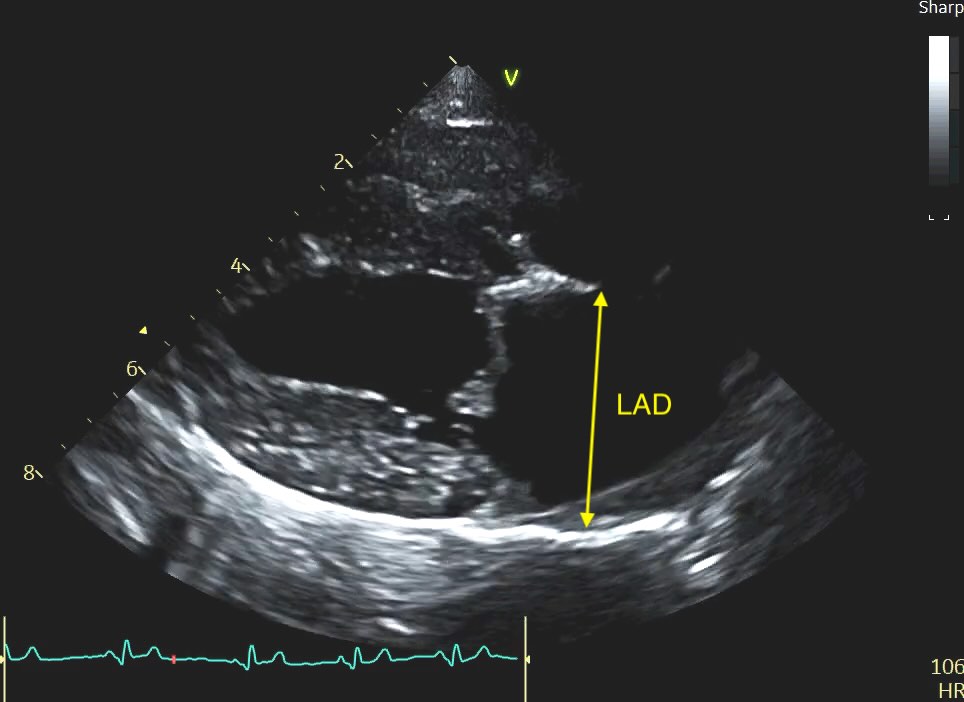

Veterinary cardiology is increasingly moving toward the Left Atrial anteroposterior Dimension (LAD). Measured from the right parasternal long-axis view, the ‘4 Chamber’ view, this metric is often more repeatable, easier to acquire in a struggling patient, and provides a clearer picture of the atrium’s true expansion.

The LAD is measured using the Right Parasternal Long-Axis 4-Chamber view (RPLA4Ch). This is often called the “heart homepage” because it allows for a comprehensive subjective and objective assessment of all four chambers simultaneously. See our article on echo views here.

Methodology and Timing

Unlike the LA:Ao, which we time to early diastole, the LAD is measured at end-systole. This is when the left atrium is at its maximal volume, having just finished filling from the pulmonary veins.

Caliper Placement:

Measure the distance from the inner wall (endocardial border) of the middle of the interatrial septum to the inner wall of the posterior free wall.

The line must be at the widest point of the atrium and must remain parallel to the mitral valve annulus.